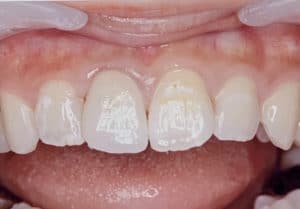

全体を覆うときには、とにかく強度があり傷が非常につきづらく、歯の削る量も少なくてすむジルコニアが合っていると思います。ただ、この素材は通常、色合わせが難しい、接着が難しい、かみ合わせ調整が難しいなど、難易度が高く、それゆえ歯科医のなかには使わない方もおられます。

当院では、色付けまでを院長が行うことで色合わせを細密に行い、時間をかけた丁寧な接着により脱離などをほぼなくし(0.5パーセント以下)、先生によるデジタル設計によりその方にあったオーダーメイドな歯の設計をすることにより、かみあわせの調整の極力小さいジルコニアを作っています。

そのことにより、ジルコニアのメリットである、傷がつきにくくツルツルした感触が非常に長く続く、削る量が小さく歯がしみにくい、噛んだ感触が自然でかみごたえがある等が、それぞれの方にいかされた歯に仕上がります。(割れにくいとれにくいは当然です!)

ジルコニアという素材は、ネットなどで検索しても見た目が今ひとつという記述が目立つと思いますが、写真のようにその方にあった色を実際にみた院長がつくること、作製になれていること、最新の技術を使っていることなどにより以前とは全く違う見た目を実現しています。

また、少しプラスのコストはかかりますが、歯科雑誌に原稿をかかれたり、歯科メーカーの技工インストラクターをつとめられます、伊藤竜馬先生とのコラボレーションによりこのような術前術後の差がわからないジルコニアを作製することも、オプションとして用意できております。